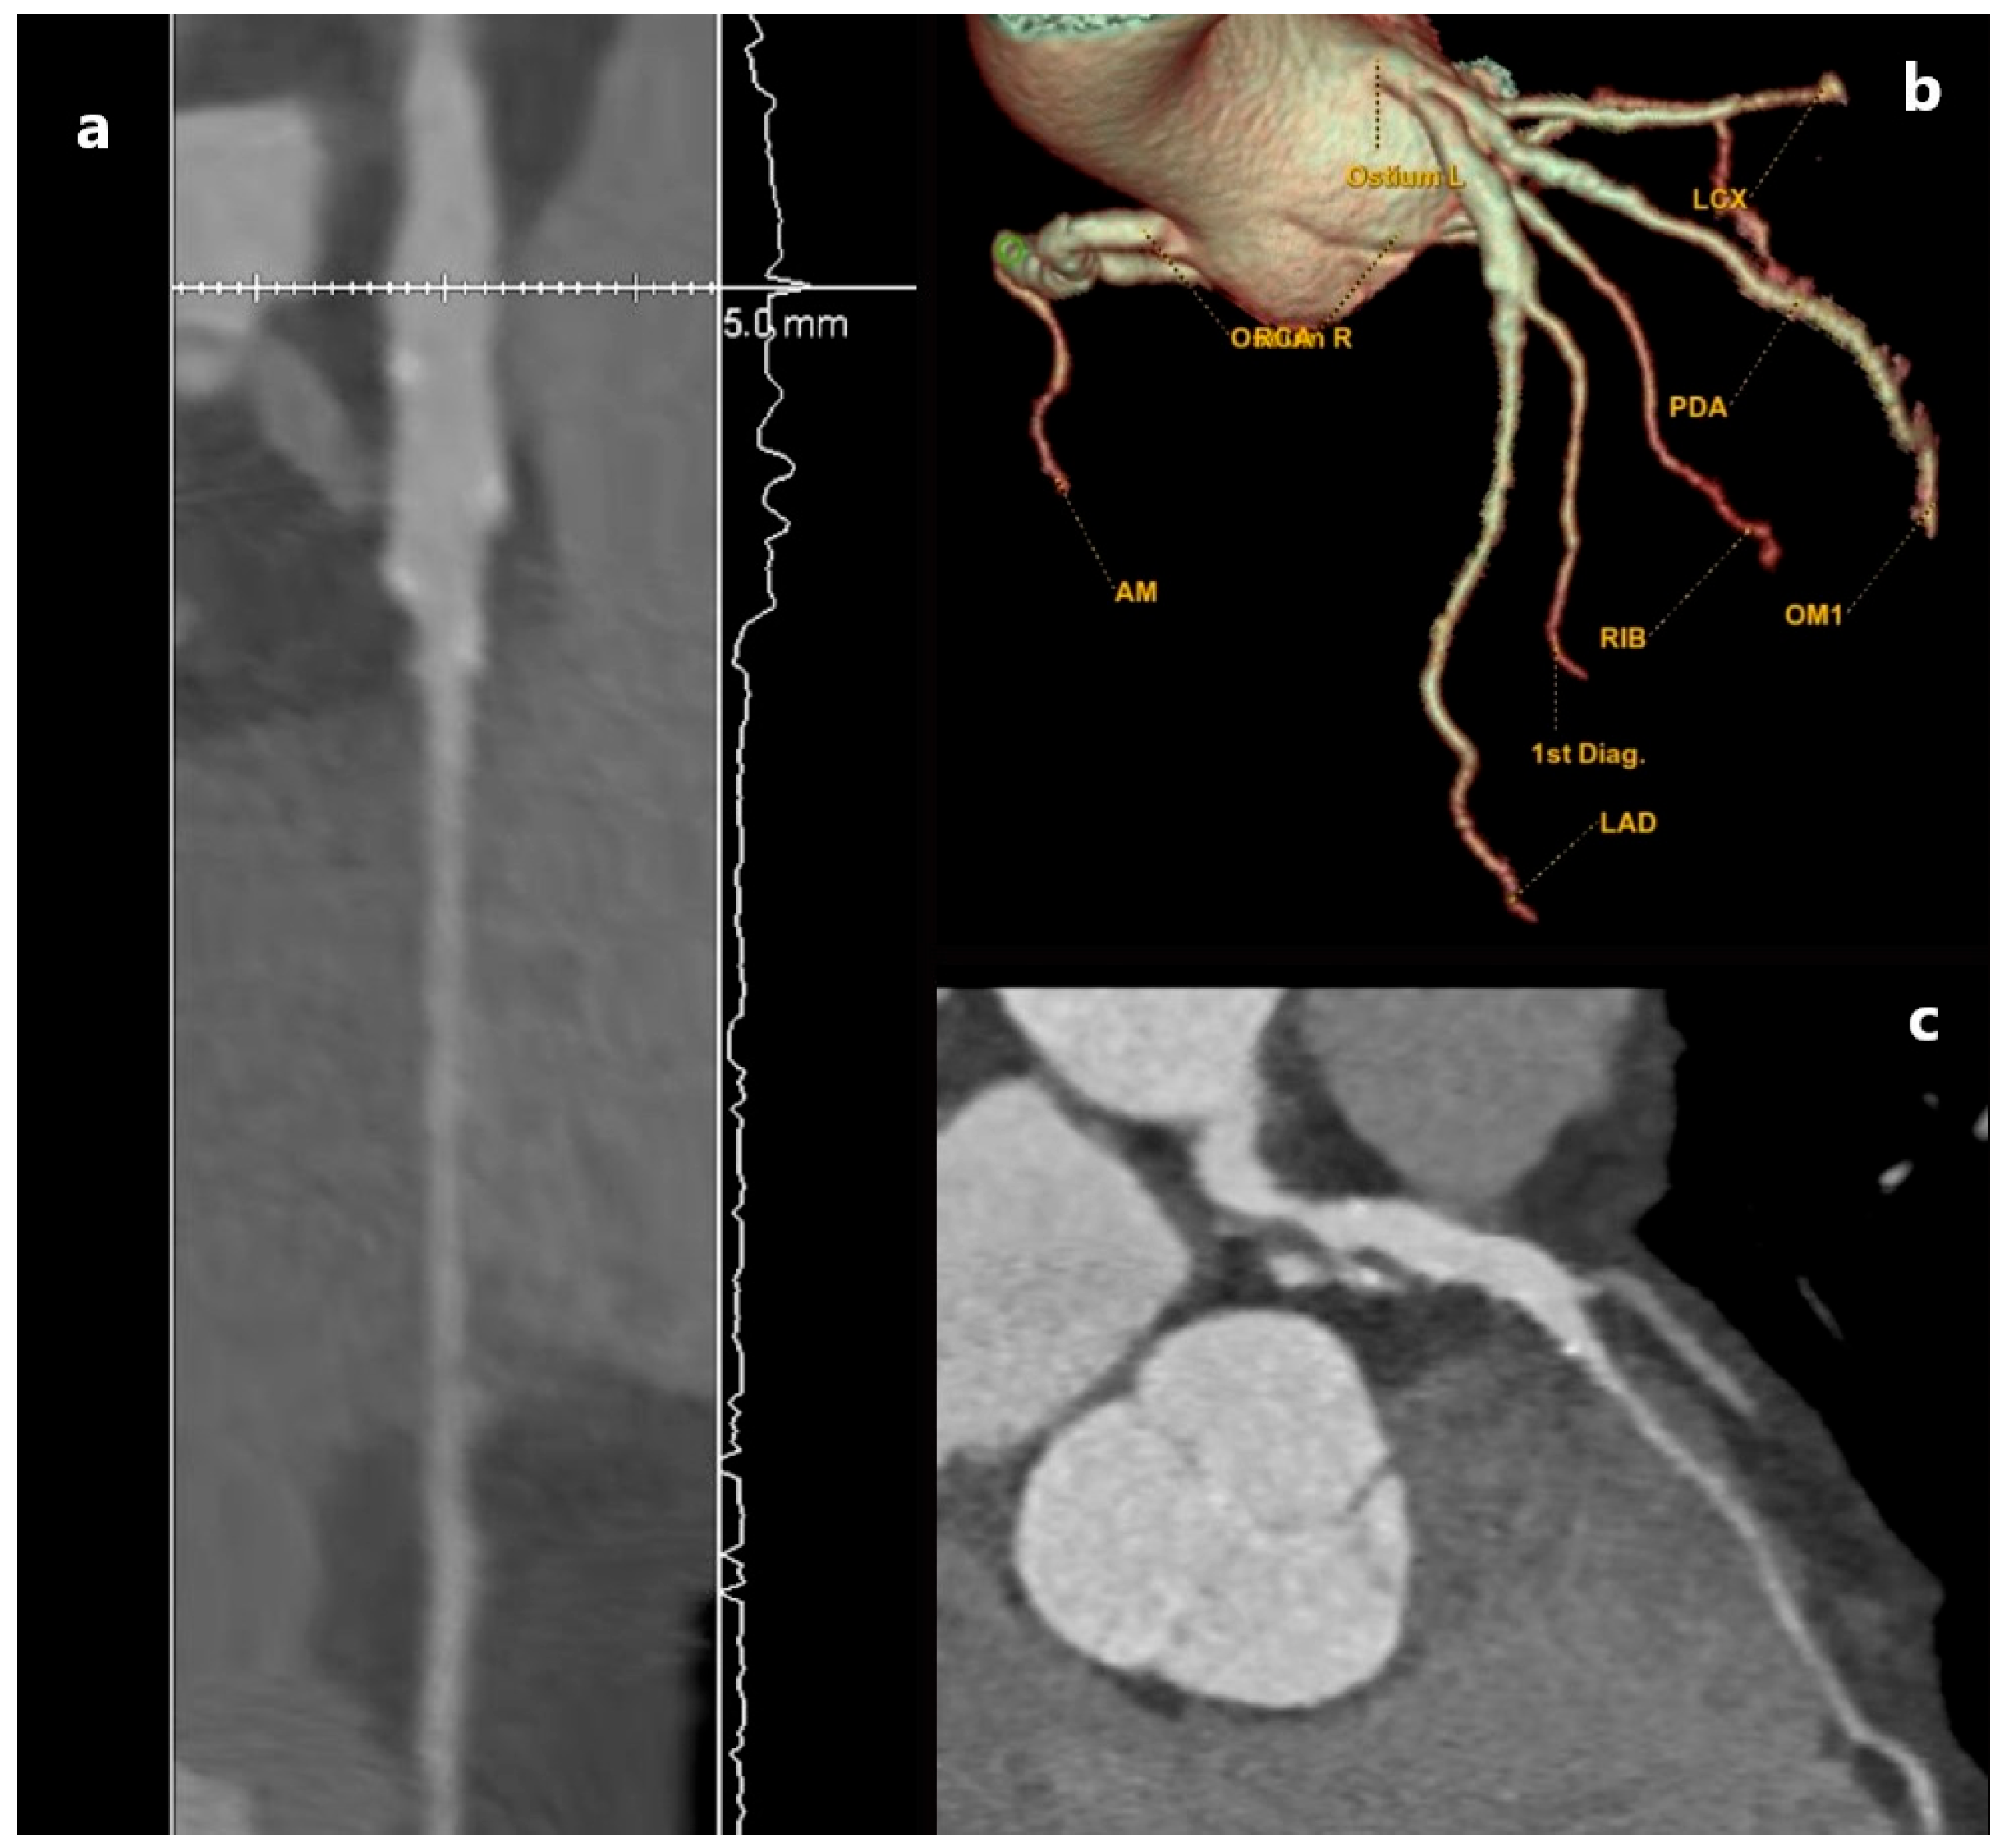

3.2. Pathological Dilatation of Coronary Arteries: Aneurysm and Ectasia